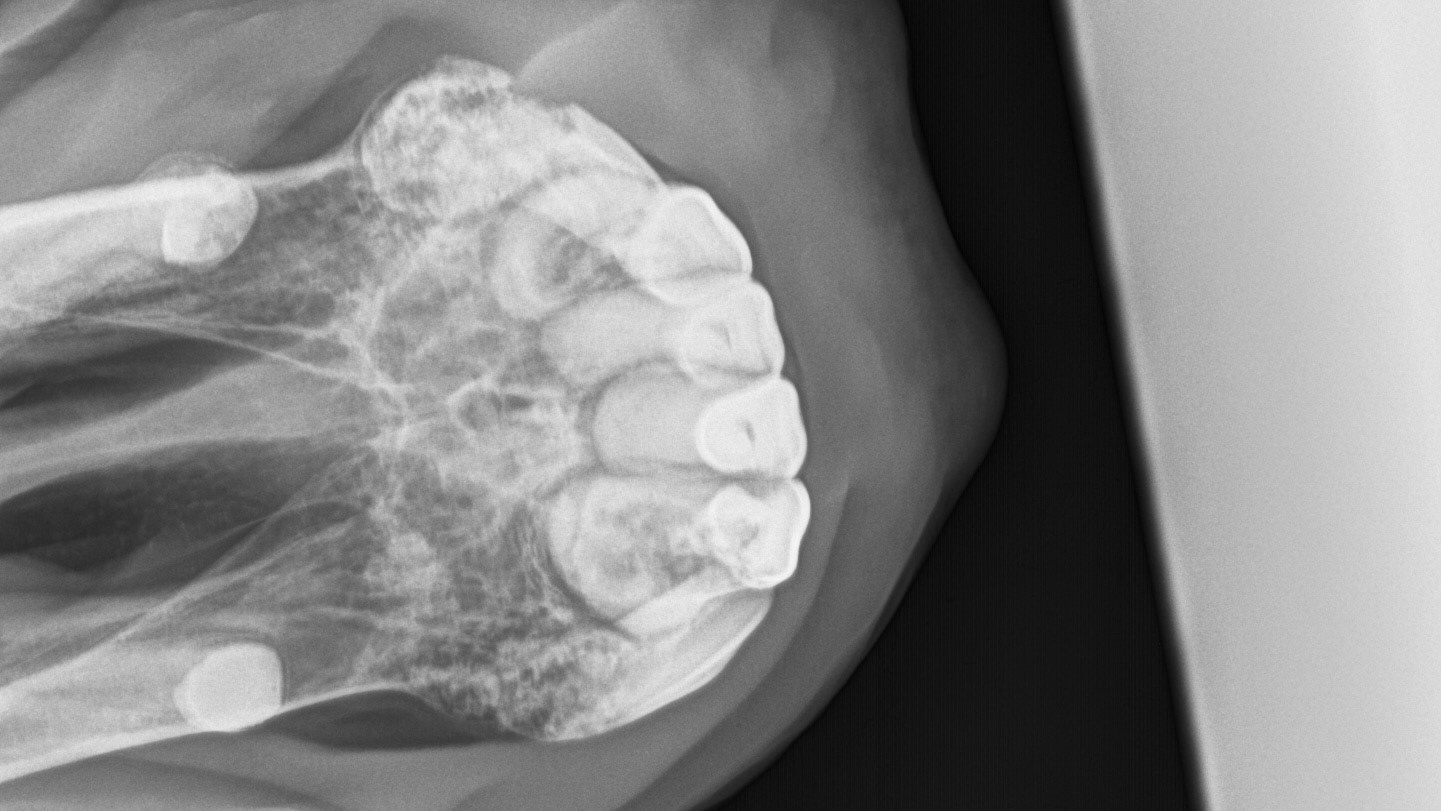

A radiograph (X-ray) of the canines and incisor teeth in a horse with EOTRH. Note the lacy look of the bone where the teeth insert as well as the enlargement of the tooth roots as they struggle to hang on.